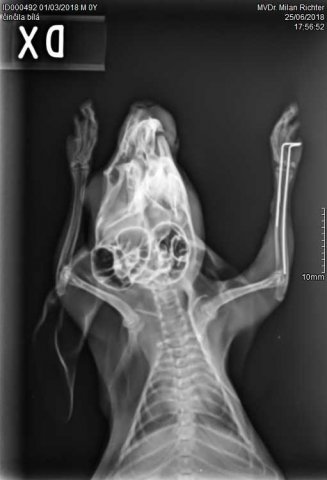

Velmi komplikovaná fraktura obou předloketních kostí u drobné činčily, jelikož se tak drobné implatáty běžně nevyrábějí, řešili jsme ji implantací nitrodřeňových hřebů vyrobených z injekčních jehel. Pacient se kompletně a bez následků uzdravil, po vyjmutí hřebů nožičku naplno používá.